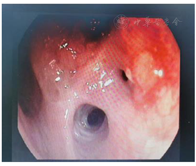

分别于2020年8月5日、2020年9月5日行卡瑞利珠单抗免疫治疗+吉西他滨(1.2 g d1)+顺铂(100 mg d1)方案化疗两周期,期间出现II度骨髓抑制,予以对症处理后好转,均未行第8天吉西他滨治疗。2020年9月行气管镜检查提示右上叶管腔内新生物消失,管腔通畅,粘膜光滑,胸部CT提示右肺下叶支气管扩张,未见新发肺部病变,疗效评价为完全缓解。故于2020年9月28日、2020年11月12日、2020年12月9日再次行卡瑞丽珠单抗联合化疗3周期,具体用药方案同前,期间患者反复出现II度骨髓抑制,予以相关处理。肝肾功能、肿瘤指标及胸部CT稳定,未见明显消化道反应及其他毒副反应。